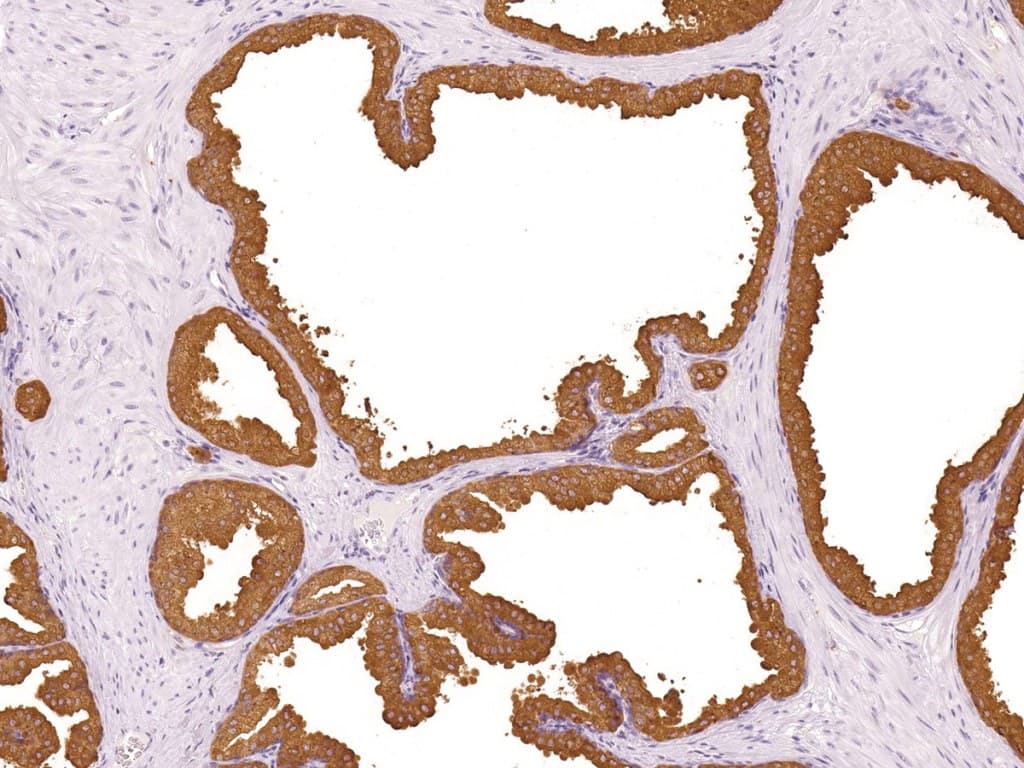

L’immunohistochimie (IHC) anti-PSAP (phosphatase acide prostatique ; PAP ; gène : ACPP) est utilisée comme marqueur d’appoint de la différenciation prostatique en pathologie génito-urinaire (GU). Elle est le plus souvent appliquée dans le contexte des carcinomes métastatiques de primitif inconnu ainsi que dans le diagnostic différentiel entre adénocarcinome prostatique et carcinome urothélial. L’expression de la PSAP est typiquement observée sous forme d’un marquage cytoplasmique dans l’épithélium prostatique bénin et dans de nombreux adénocarcinomes prostatiques conventionnels (acineux).

- Caractéristiques analytiques : Les anticorps monoclonaux anti-PSAP sont appliqués sur des tissus fixés au formol et inclus en paraffine (FFPE) avec récupération antigénique par chauffage (heat-induced epitope retrieval) et détection par système polymérique, produisant un marquage cytoplasmique de l’épithélium prostatique.